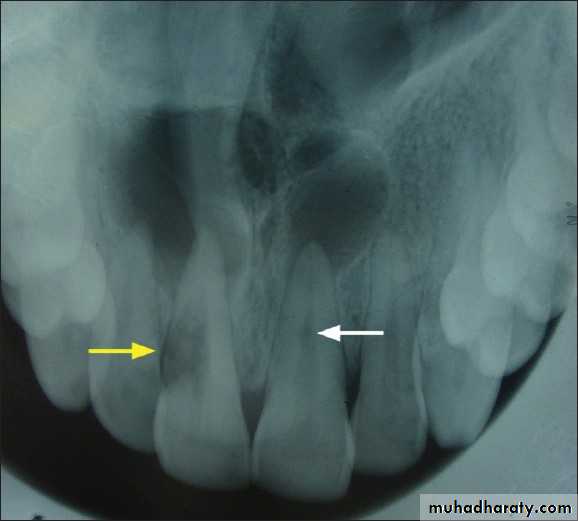

• Clinically:“Pink Tooth” appearance• Radiographic changes:

– Radiolucent enlargement of pulp canal

– Original root canal outline distorted

– Bone changes are seen only when root perforation into periodontal ligament takes place.